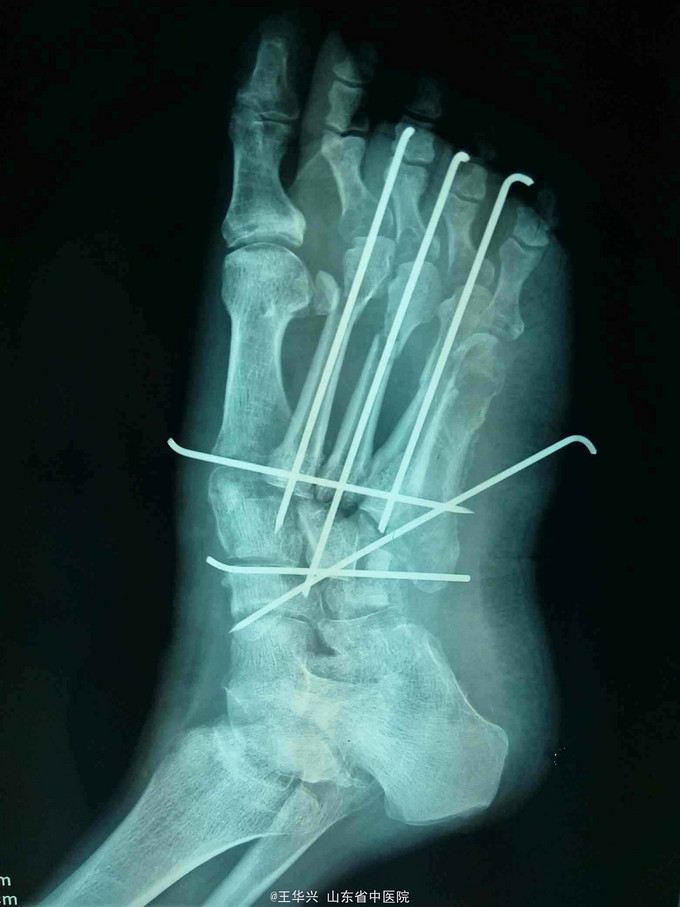

诊断:左足毁损伤 治疗:入院时已达到截肢标准,但患者家属不能接受,遂行常规手术。多次清创,行急症手术,给予简单钛针固定,软组织损伤给予原位缝合。细菌培养结果,万古霉素敏感,万古霉素局部填塞创口换药,术后给予多次清创,清除坏死组织及vsd负压吸引。待左足缺损区软组织条件可,行交腿皮瓣。